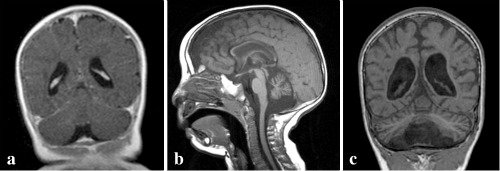

The figures depict the progressive wasting away of brain tissue, beginning with normal appearance at eight months (left), moving to progressive loss of brain tissue by 18 months (middle) and then at three years (right).

“The full name of the disease is Progressive Cerebro-Cerebellar Atrophy (PCCA), in which there is a genetically-determined, progressive wasting away of cells throughout the brain,” Birk tells ISRAEL21c, adding that “affected individuals have psychomotor retardation which is severe by one to two years of age, and spasticity (stiffness of the body, especially arms and legs). Most also have epilepsy.”